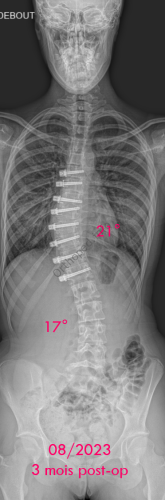

Images de scolioses opérées 16 janvier 202418 janvier 2023 par Damien Scoliose idiopathique - VBT -1 Chirurgie de modulation de croissance (VBT) Scoliose idiopathique - VBT -1 - pré-op Scoliose idiopathique - VBT -1 - pré-op en traction Cliché réalisé pour tester la réductibilité de la scoliose Scoliose idiopathique - VBT -1 - post-op immédiat Scoliose idiopathique - VBT -1 - 3 mois post-op Scoliose idiopathique - VBT -1 - 10 mois post-op